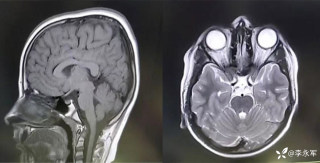

昨天值班遇到的一例晕厥病例,差点漏诊,而最终的解法,始于最简单而质朴的查体。国庆中秋双节的最后一天,8号的早上8点,抢救室床旁晨交班,病人依旧是多而重,交到6床,一个刚入室不久的病人,准备去做CT,夜班医师汇报病史:69岁男性,本次因“头晕伴一过性晕厥1小时”为主诉入抢,1小时前于高铁站因即将赶不上高铁走路快时突发头晕,伴一过性晕厥,约3-4分钟后清醒,清醒后诉今晨未吃早餐,已服用降压药物,仍有头晕头痛、四肢乏力等不适,无胸闷胸痛,无畏寒发热,无咳嗽咳痰,无恶心呕吐,无肢体麻木,无视物模糊等不适,路人拨打120送至我院急诊就诊。既往高血压,长期服用氨氯地平+福辛普利,血压控制一般;糖尿病,长期